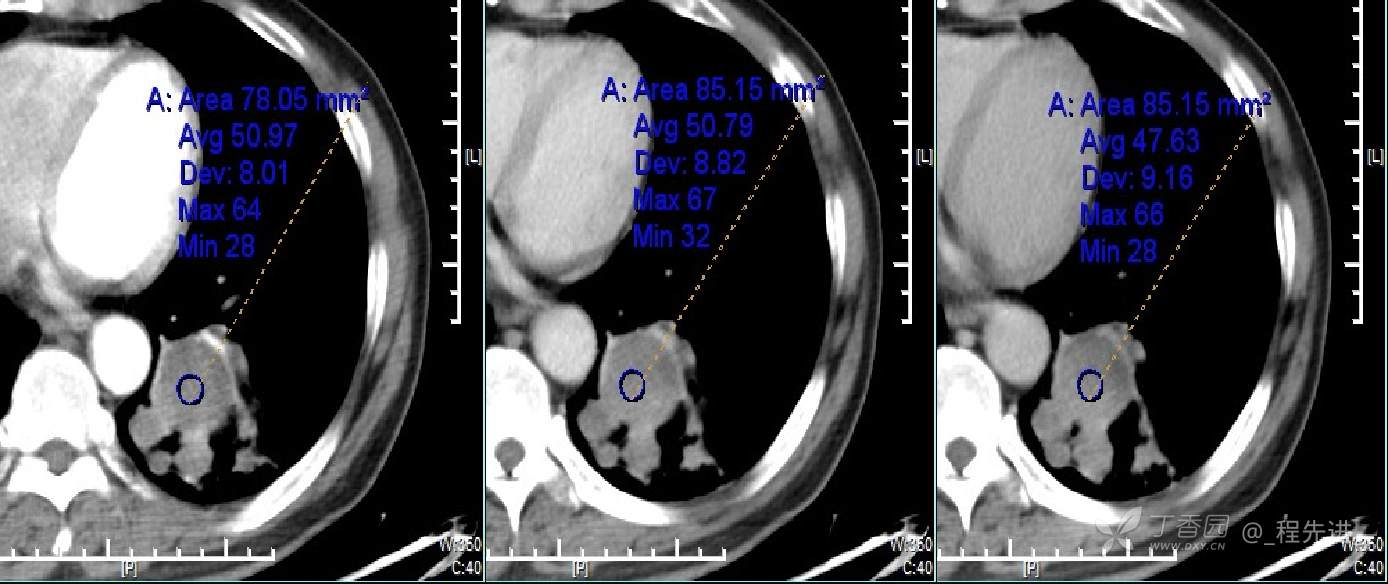

患者性别:男

患者年龄:70岁

简要病史:咳嗽不适1月余,痰中带血7天,胸片发现左肺下叶占位直接做CT增强扫描